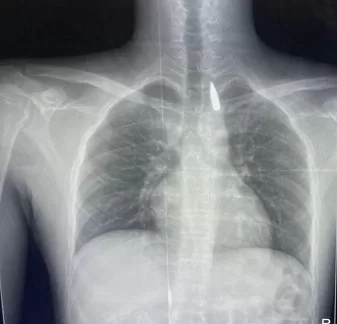

الذي كان قد تعرض لإصابة بطلق ناري في الرأس منذ فترة إستقر المقذوف على إثرها داخل تجويف القفص الصدري قرب الشريان الأورطي وهو أكبر وأهم شرايين الجسم والمسؤول عن تغذية جميع الأعضاء الحيوية

فيما كشف الدكتور تامر عبد الله عميد كلية الطب ورئيس مجلس إدارة المستشفيات الجامعية أن الفريق الطبي نجح في إستخراج المقذوف بأمان بعد عملية جراحية نادرة إستمرت عدة ساعات داخل المستشفى الجامعي الجديد حيث خضع المريض بعدها للرعاية الطبية اللازمة وحالته حاليًا مستقرة وتحت المتابعة الدقيقة من الفريق المختص